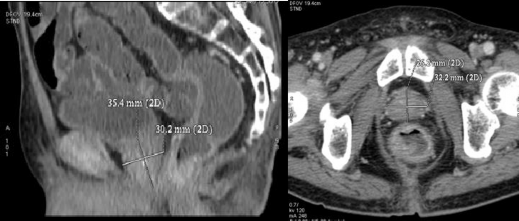

Chụp cộng hưởng từ:

- Tiền liệt tuyến phì đại, phần phì đại nằm ở thùy trung tâm và ngoại biên kích thước 53 x 47 x 46 mm bờ không đều tín hiệu không đồng nhất có nhiều nốt tăng tín hiệu trên xung DWI ở ngoại biên và ngấm mạnh và không đồng nhất thuốc đối quang từ sau tiêm tổn

thương đã phá vỡ vỏ và xâm lấn vào túi tinh bên phải và lớp mỡ quanh tuyến .

- Bàng quang thùy ngoại biên bên trái phát triển lồi vào thành bàng quang

- Nhiều hạch quanh bó mạch chậu, hạch lớn nhất 12 x 20 mm

Kết luận: Theo dõi ung thư tiền liệt tuyến có xâm lấn túi tinh phải và nhiều hạch bẹn và hạch chậu

điểm

Hình A. Hình ảnh chụp cộng hưởng từ khi vào viện